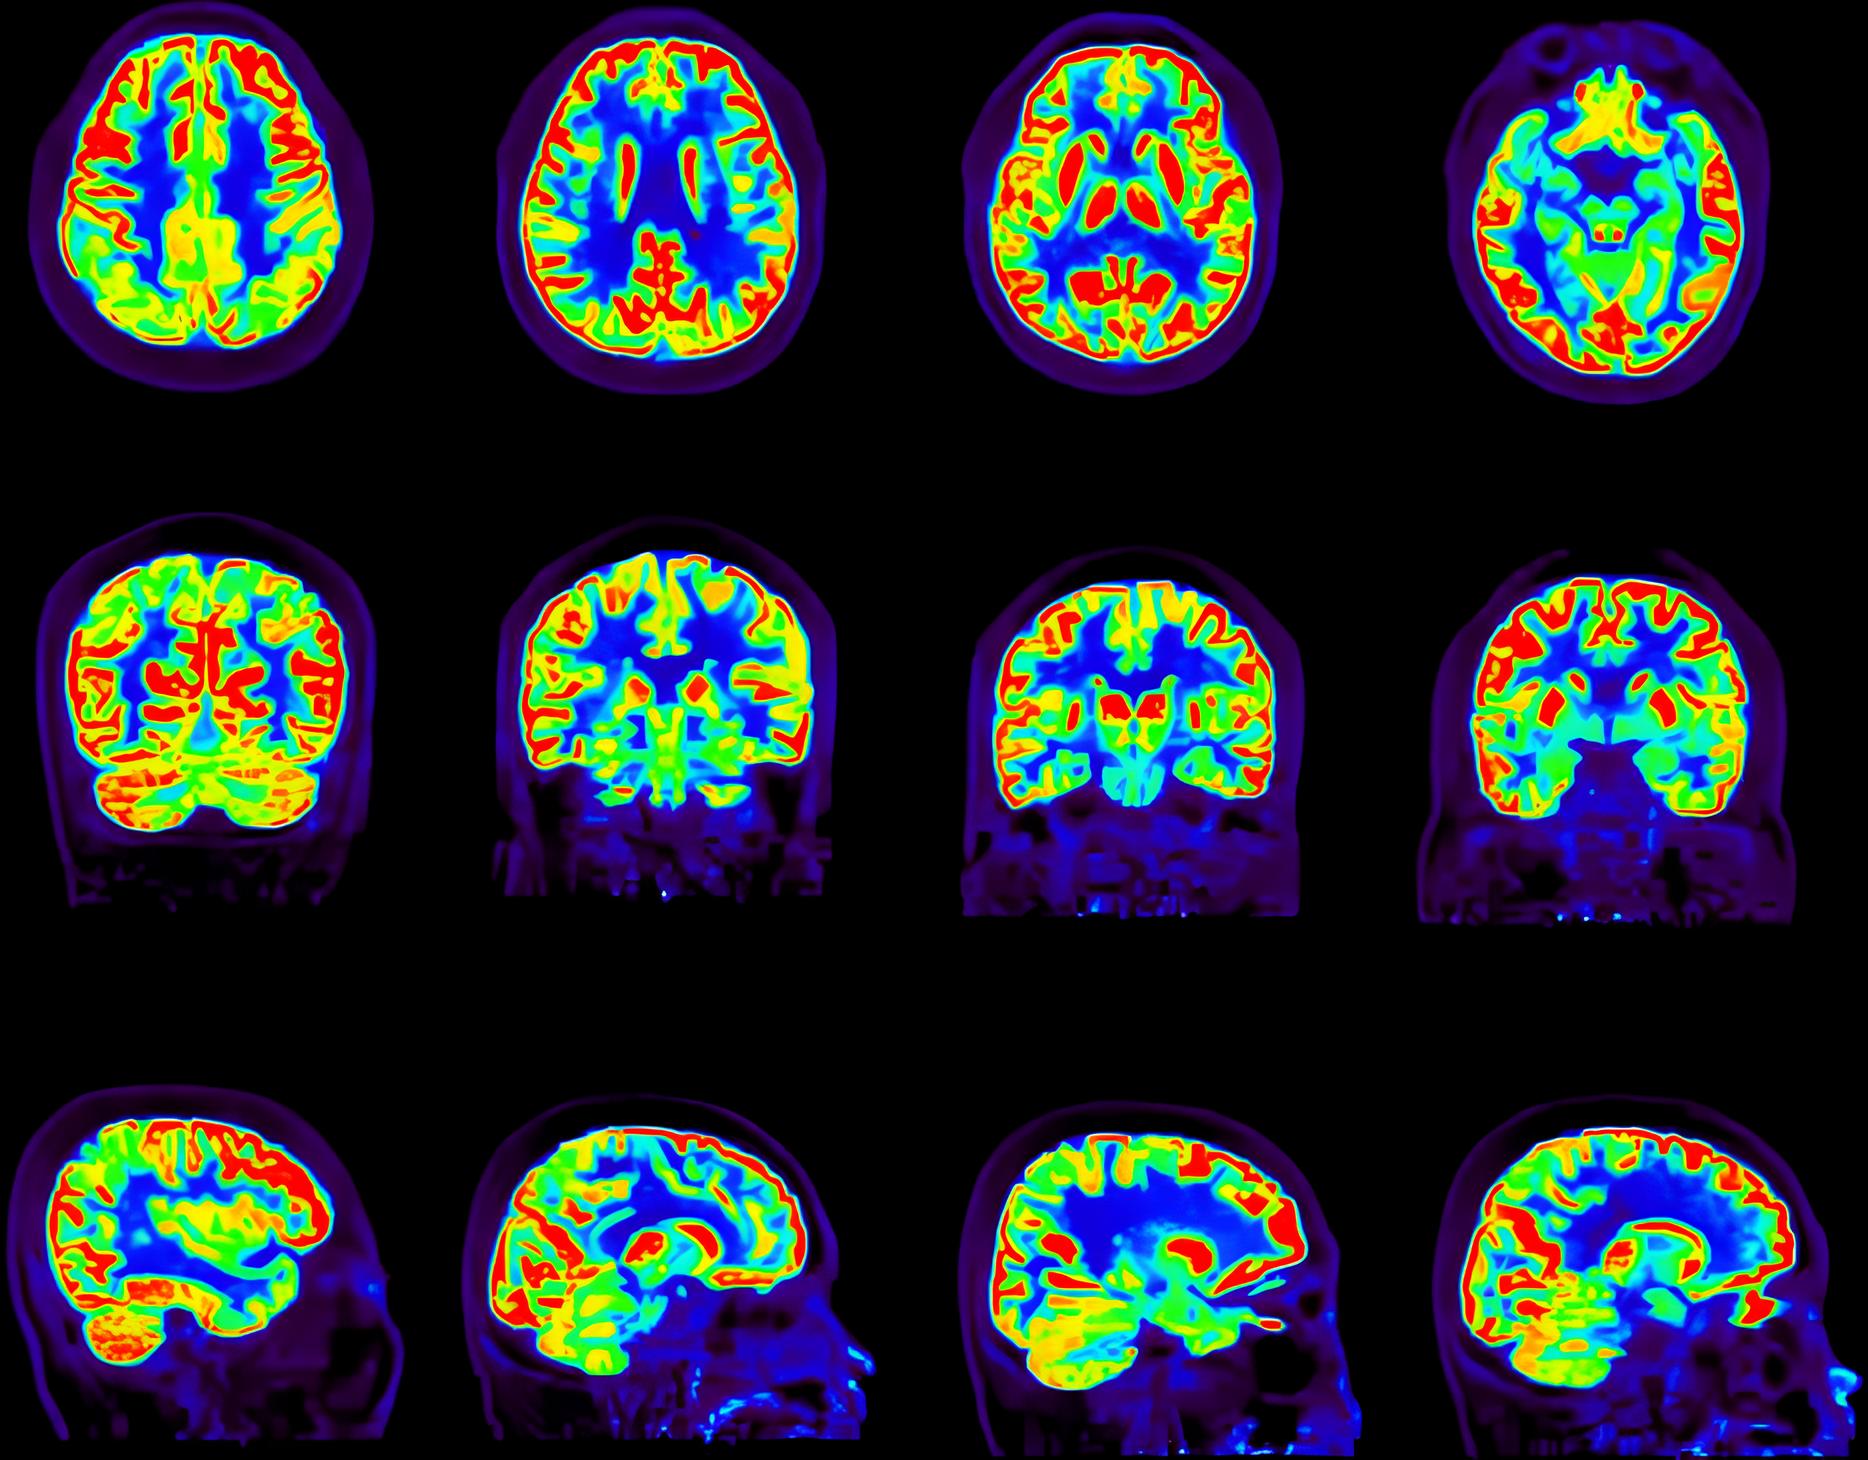

图像重建研究基于全数字PET技术全采样、全数据特性,致力于建立全数字PET重建理论,为临床PET、动物PET,以及质子刀PET、头盔PET等应用专用PET研发智能重建方法。研究内容集中在高性能图像重建算法和全流程数据校正算法,将PET重建性能指标推向物理极限;同时面向变结构重建方法、电子偶素成像方法、全伽马成像方法和PET-SPECT成像方法展开前沿探索,为PET重建开辟新的可能性。图像重建研究组为临床和临床前PET应用竞争力的持续提升提供源源不断的算法支持,持续推动PET重建向更准、更智能的方向演进。

全采样重建

采用单事件、低能量事件等全流程数据进行全数字PET图像重建,解决低剂量、多核素等场景下高质量成像问题。